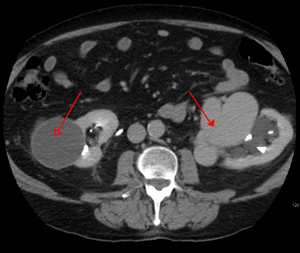

يتم تشخيص التشوه الشرياني الوريدي بشكل أساسي من خلال طرق التصوير التالية:

- التصوير المقطعي المحوسب (CT) هو عبارة عن أشعة سينية غير باضعة لعرض الهياكل التشريحية داخل الدماغ لاكتشاف الدم في الدماغ أو حوله. تتضمن تقنية أحدث تسمى تصوير الأوعية المقطعية المحوسبة حقن التباين في مجرى الدم لعرض شرايين الدماغ. يوفر هذا النوع من الاختبارات أفضل صور الأوعية الدموية من خلال تصوير الأوعية والأنسجة الرخوة من خلال التصوير المقطعي المحوسب.

- يعد التصوير بالرنين المغناطيسي (MRI) اختبارًا غير باضع ، يستخدم مجالًا مغناطيسيًا وموجات تردد الراديو لإعطاء رؤية مفصلة للأنسجة الرخوة للدماغ.

- تصوير الأوعية بالرنين المغناطيسي (MRA) - فحوصات تم إنشاؤها باستخدام التصوير بالرنين المغناطيسي لتصوير الأوعية الدموية وهياكل الدماغ على وجه التحديد. يمكن أن يكون تصوير الأوعية بالرنين المغناطيسي إجراءً جائرًا ، يتضمن إدخال صبغات التباين (على سبيل المثال ، عوامل تباين الجادولينيوم MR) في الأوعية الدموية للمريض باستخدام قسطرة يتم إدخالها في الشريان وتمريرها عبر الأوعية الدموية إلى الدماغ. بمجرد وضع القسطرة في مكانها ، يتم حقن صبغة التباين في مجرى الدم ويتم التقاط صور التصوير بالرنين المغناطيسي. بالإضافة إلى ذلك أو بدلاً من ذلك ، يمكن استخدام تقنيات التصوير بالرنين المغناطيسي المعتمدة على التدفق أو غيرها من تقنيات التصوير بالرنين المغناطيسي لتحديد الموقع والخصائص الأخرى للأوعية الدموية